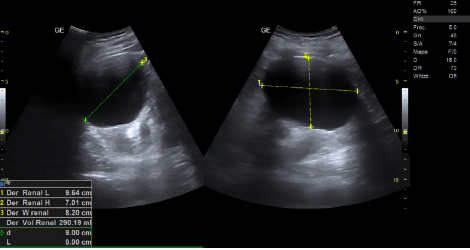

- Ecografía clínica renovesical: Vejiga sin lesiones ocupantes de espacio, sin residuo postmiccional, próstata de tamaño aumentado (56 cc). Ambos riñones con quistes corticales simples, de hasta 9,6 cm en el riñón izquierdo. Sistema excretor derecho no dilatado. Leve-moderada dilatación pielocalicial izquierda. No se evidencian imágenes ecográficas sugestivas de litiasis en pelvis renal.

- Resonancia magnética renal con contraste: hidronefrosis grado II izquierda, secundaria a litiasis obstructiva de 5 mm localizada en el tercio inferior del uréter, inmediatamente caudal al cruce con los vasos ilíacos. Quistes sinusales y simples corticales bilaterales, el mayor de 9,4 cm de eje craneocaudal en el polo inferior del riñón izquierdo. Resto sin alteraciones significativas.